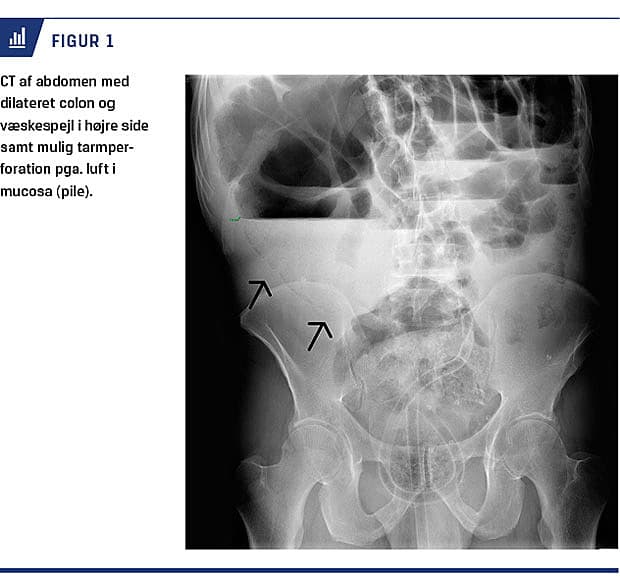

På mistanke om colon ileus blev der foretaget CT med intravenøs kontrast af abdomen, hvorved man fandt sigmoideum volvulus og en dilateret caecum på 12 cm i diameter. Der blev foretaget sigmoideoskopi med desufflering af colon med nogen effekt. Pga. tiltagende abdominalomfang dagen efter trods desufflering gentog man CT af abdomen, og resultatet rejste mistanke om tarmperforation pga. en gendannet sigmoi-deumvolvulus og en stadig dilateret caecum (Figur 1). Patienten blev akut opereret, og man fandt synkron caecum- og sigmoideumvolvulus. Colon var præget af kronisk dilatation, og caecums diameter var ca. 15 cm med flere serosalæsioner. Ved operationen blev der foretaget total kolektomi og anlæggelse af en ileostomi. Patienten blev udskrevet i velbefindende på den tiende postoperative dag.